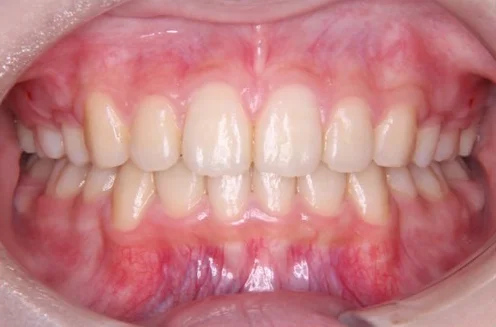

治療後

| 相談内容(主訴) | 前歯のガタガタが気になる |

|---|---|

| 診断結果/行った治療内容 | 叢生/アクティビティ+インビザライン矯正 |

| 治療期間/回数 | 1.5年/18回 |

| 治療費用 | 50万円(マイオブレイス+インビザライン)+アクティビティ 月一5,500円 |

| 治療のリスク/副作用 | 原則の装着時間を守らないと効果が出ません/まれに顎関節に症状が出ることがあります |